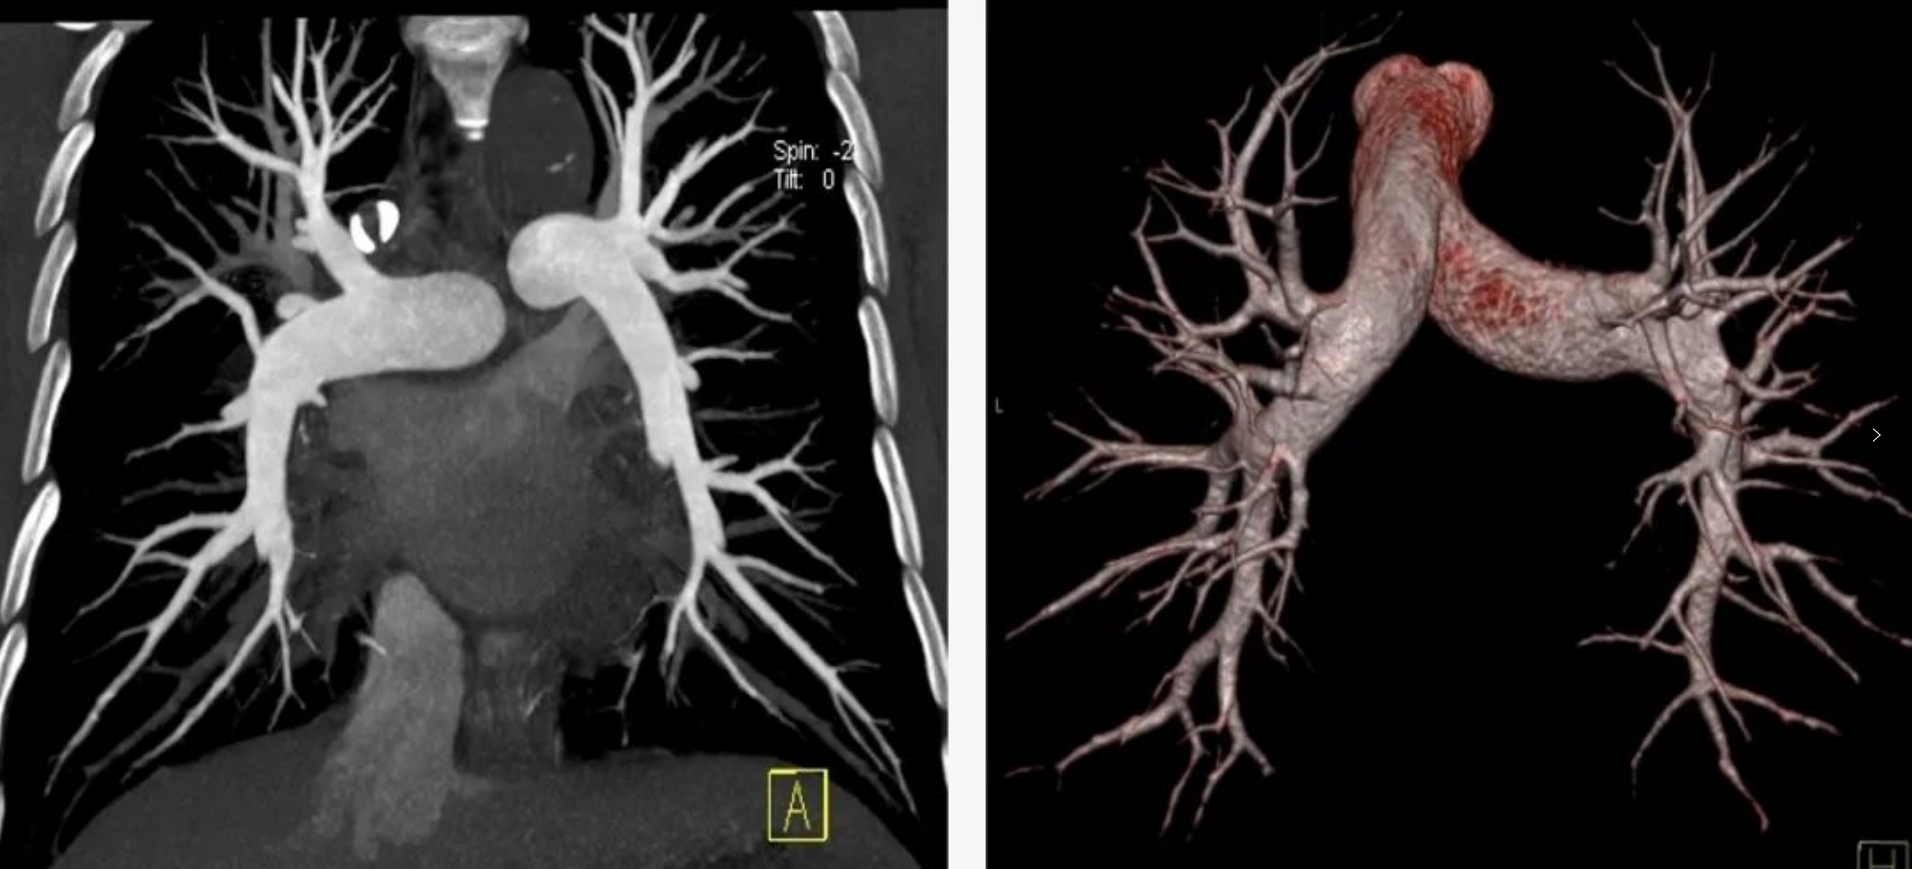

本次引進(jìn)的全新64排128層人工智能螺旋CT具有檢查更加精細(xì)、圖像更加清晰、掃描速度快和輻射劑量小等多種優(yōu)點(diǎn)。除了可進(jìn)行常規(guī)CT檢查、普通增強(qiáng)CT檢查外,還可對(duì)全身大血管、腦血管、心臟血管進(jìn)行檢查;強(qiáng)大的三維重建功能可發(fā)現(xiàn)普通DR、常規(guī)CT所難確診的病變。

用該設(shè)備做心血管系統(tǒng)檢查,能得到對(duì)比度極佳的血管圖像。大大提高了診療的精準(zhǔn)度及工作效率,有利于醫(yī)生及早發(fā)現(xiàn)微小病灶。

該設(shè)備,可以在短時(shí)間完成對(duì)冠狀動(dòng)脈缺血、肺栓塞、主動(dòng)脈瘤的一站式檢查,也可在在短時(shí)間完成對(duì)頭部血管、頸部血管、腦實(shí)質(zhì)血液灌注的一站式檢查,為腦卒中和急性胸痛患者的早期診斷和治療能力贏得黃金時(shí)間。